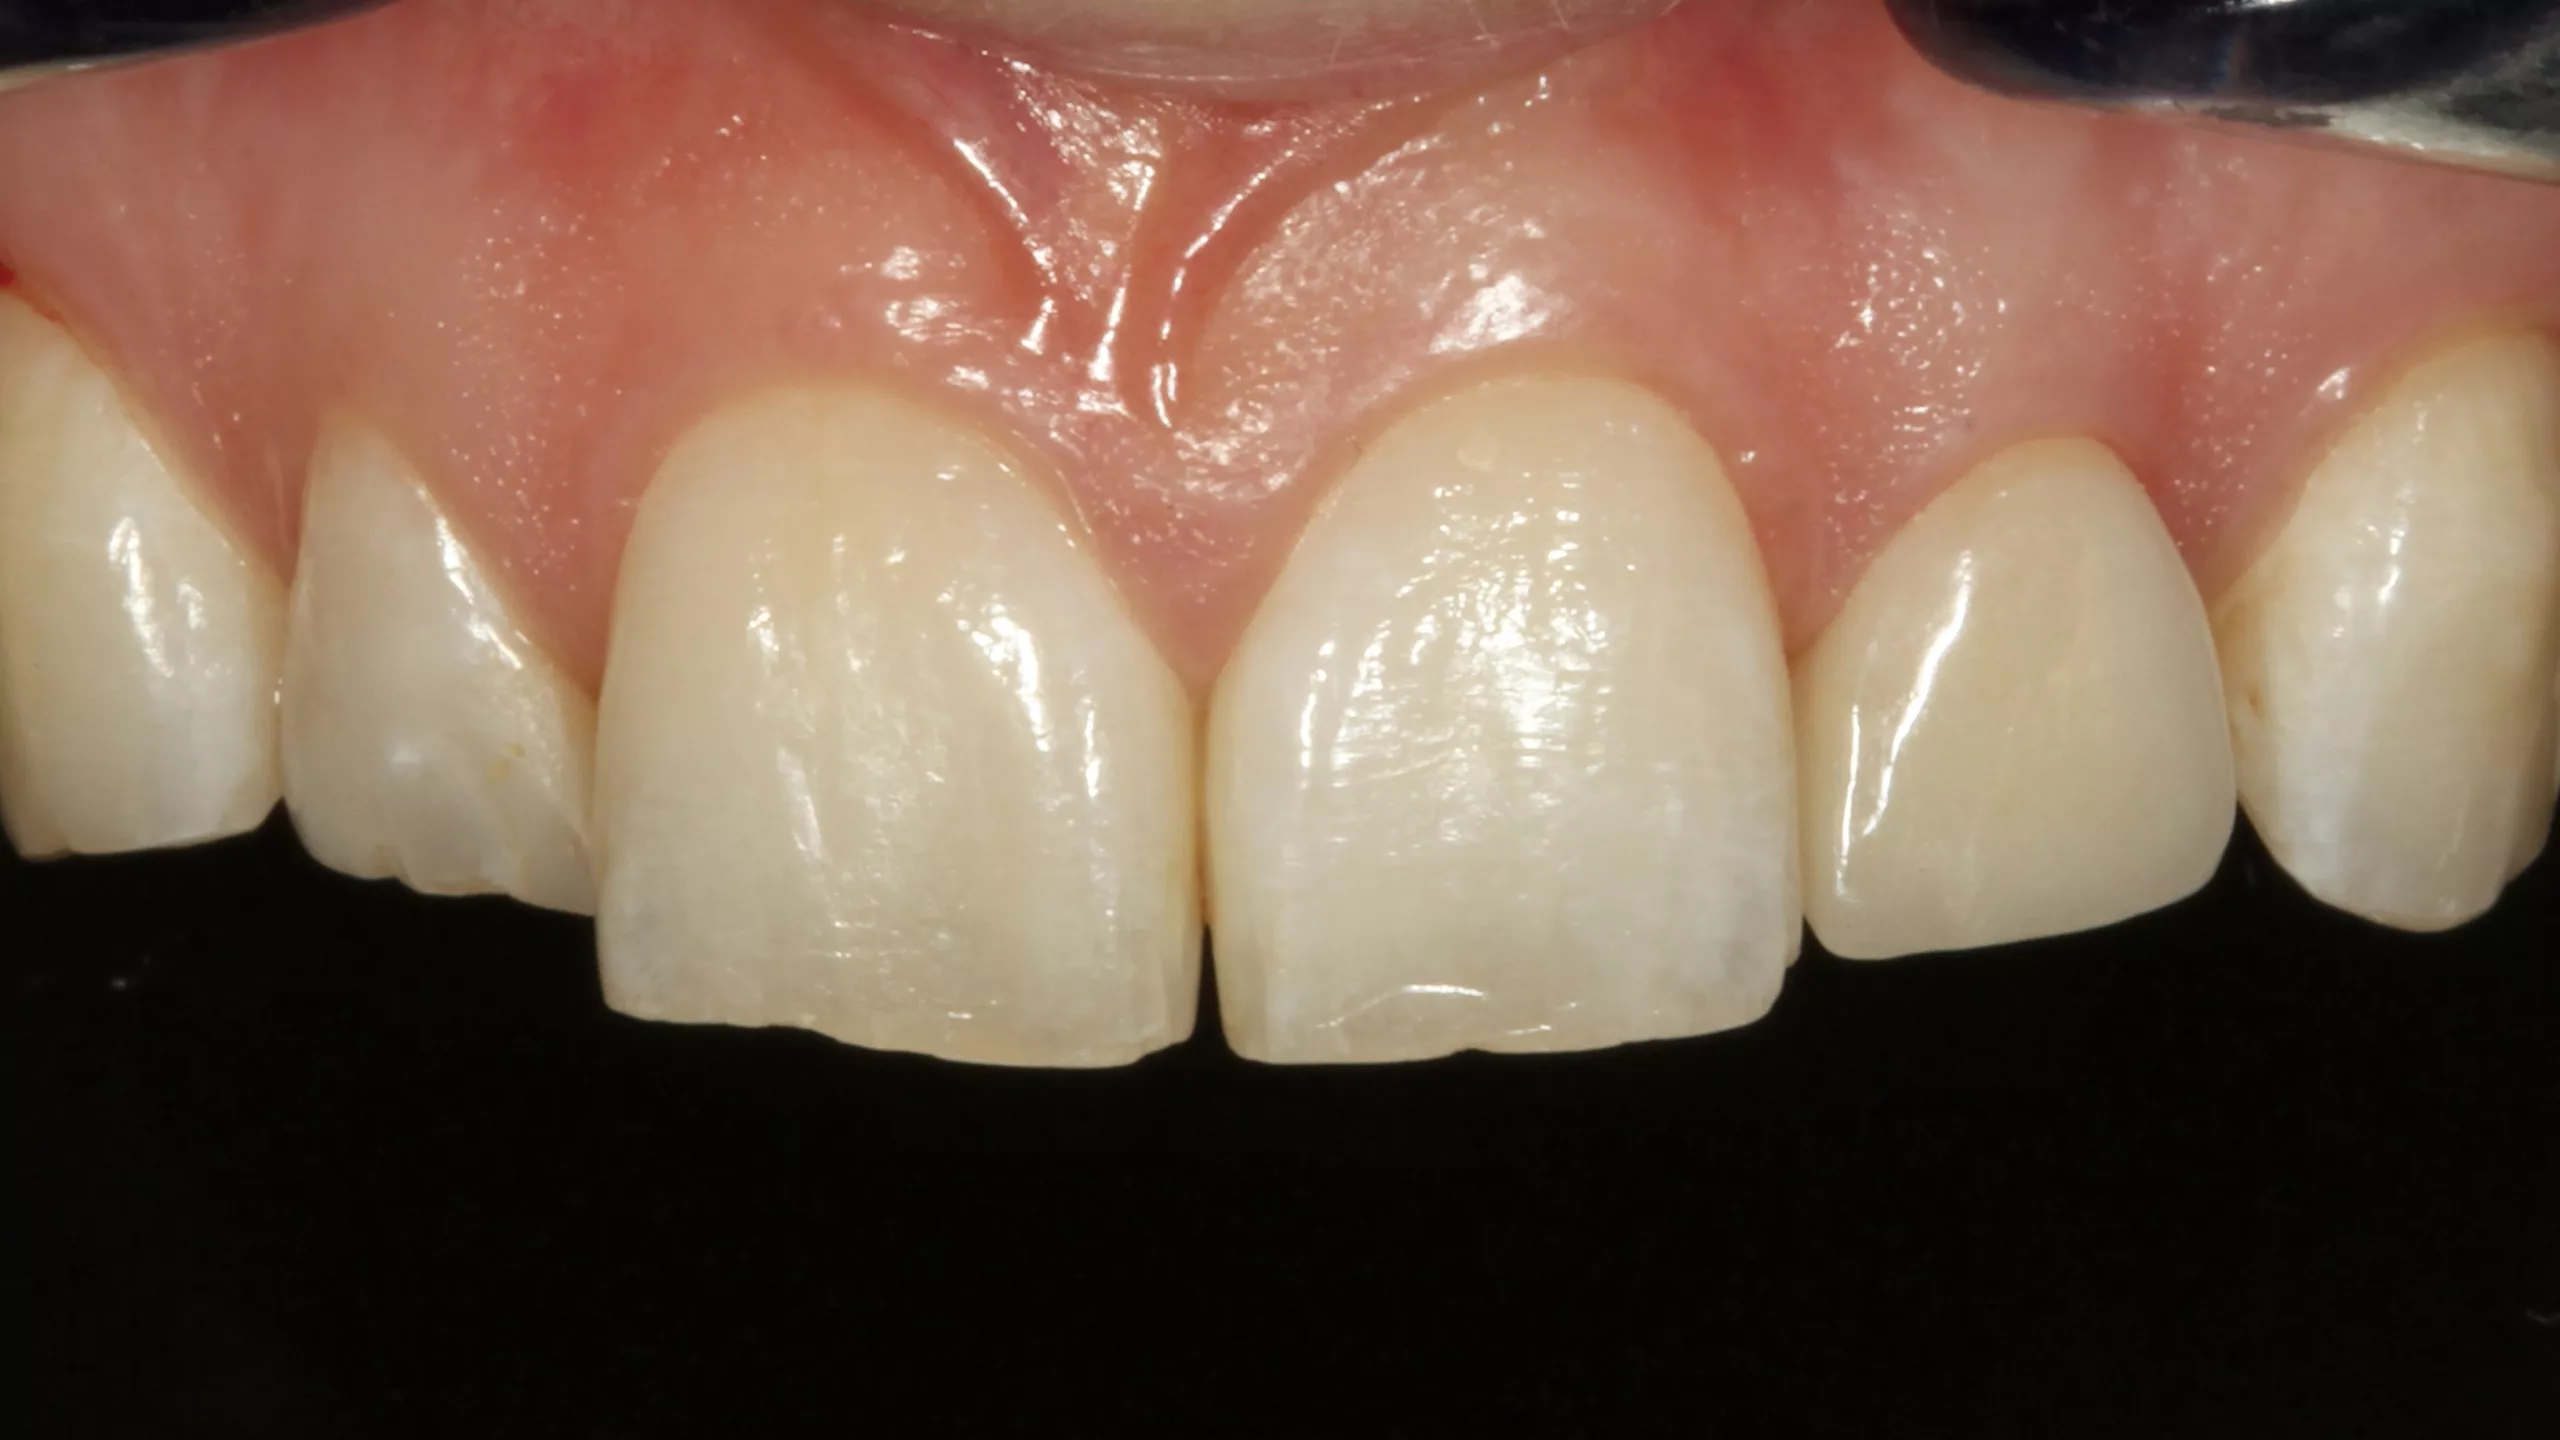

Die Abbildung 19 zeigt den bereits mit Kofferdam isolierten Zahn 22 nach der Reinigung der Oberfläche, die Abbildung 20 die Phosphorsäurekonditionierung der gesamten Klebefläche (Schmelz- und Dentinareale ließen sich nur schwer voneinander optisch differenzieren). Da der Visalys Tooth Primer auf mit phosphorsäuregeätztem Dentin genauso effizient funktioniert wie in seiner originären, selbstkonditionierenden Primerfunktion, sollte im Zweifelsfall besser großräumiger mit dem Phosphorsäuregel geätzt werden. Die Abbildung 21 zeigt den konditionierten Zahnstumpf aus inzisaler Sicht, die Abbildung 22 von labial. Wie in allen vorangegangenen Fällen erfolgte im nächsten Schritt die Applikation des Visalys Tooth Primers, dessen Einwirken für 20 Sek. (Abb. 23 und 24) und das Verblasen der Überstände bzw. die sorgfältige Evaporation des Lösungsmittels mit dem Luftbläser. Mit diesem Schritt war die Vorbehandlung des Zahnes abgeschlossen. Auch diese Krone wurde mit Visalys CemCore in der Farbe Universal (A2/A3) adhäsiv befestigt. Die vollständige Überschussentfernung erfolgte erneut mit einem sauberen Bondingpinsel (kein Microbrush) noch vor der Polymerisation (Abb. 25). Die Abbildung 26 zeigt die versäuberte, eingeklebte verblendete Vollzirkonkrone noch unter Kofferdam, die Abbildungen 27 und 28 das finale klinische Gesamtergebnis der sehr zufriedenen Patientin.